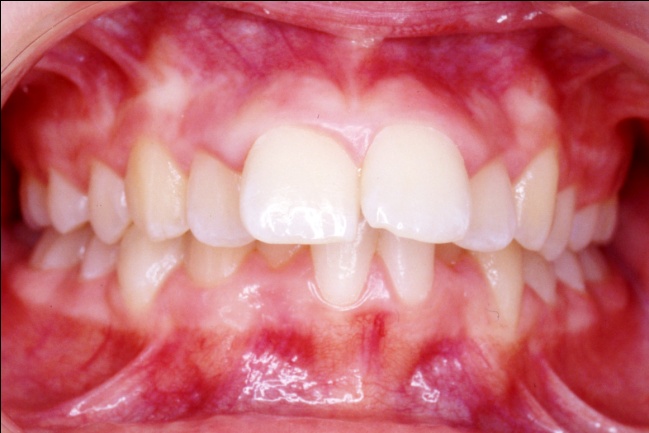

1 - Arcades dentaires avant-après traitement

Les photos montrent, avant traitement, des dents supérieures projetées vers l’avant et encombrées. Après traitement, les arcades, ayant subi l’extraction de prémolaires, présentent un articulé redevenu normal et un alignement complet. Ce résultat positif ne reflète pourtant pas toute l’ampleur des changements : en orthodontie, les dents soutiennent directement les lèvres, et toute modification de leur position influence le profil. Ici, le repositionnement dentaire a eu un effet déterminant sur l’harmonie des tissus mous.